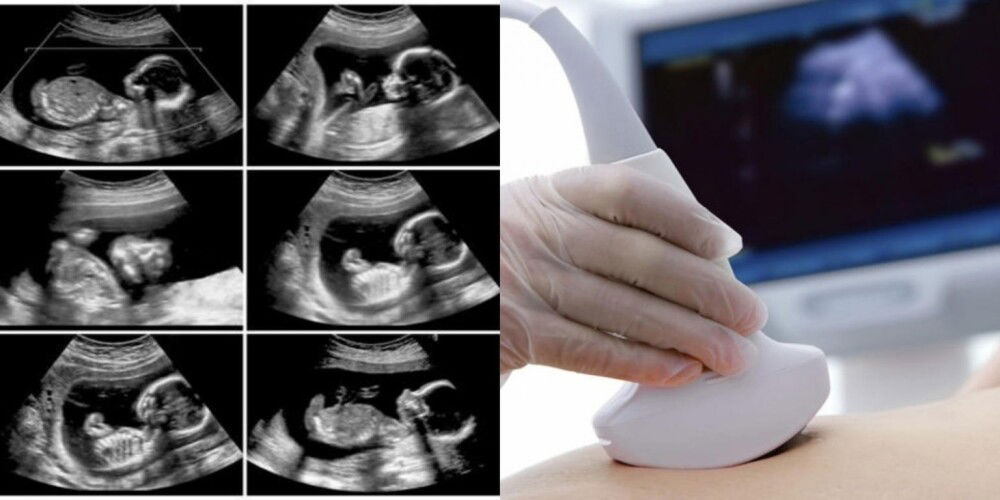

Bagi pendapat anda, penting atau tidak untuk melakukan detail scan pada bayi dalam kandungan?